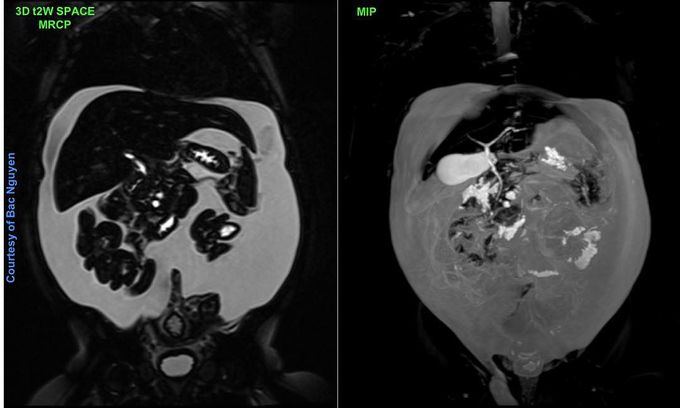

Ascites @ Siemens 1.5T Aera#Siemens_MRI #siemens #mri #abdominal_liver